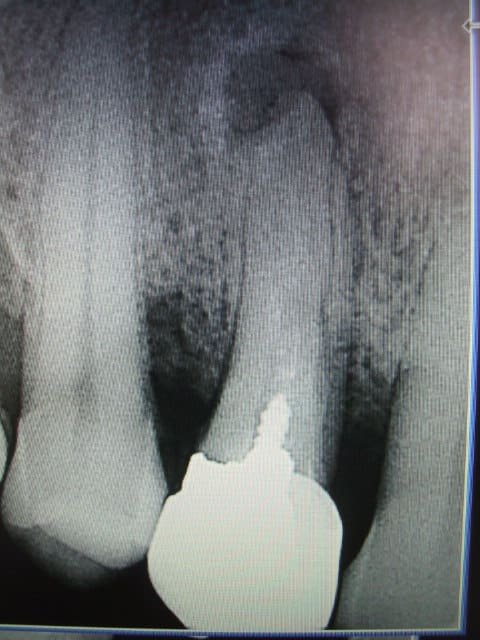

Aller 2 petites nouvelles pour le dessert

allez on ressaye -------------------------------------adhoc t'es un frère pour moi-------------------et t'as vu y a de la couleur----------------------avant tout promettez moi de ne pas en parler à Raoul,il pourrait avoir une mauvaise image de la dentisterie française et cela pourrait faire tourner le lait des kangourouses-------------------revenons au sujet, que faire?? :ED OU HN? Attendre le mois de mai?appeler la cnsd ou l'ujcd? y a plus personne.Peut etre mon comptable? prendre un avocat?appeler le dentiste conseil?Je me faire remarquer? je risque un controle?que dire au patient?adhoc m'a dit tte vérité n'est pas bonne à dire. Je risque de passer pour un collabo?Ou faire une dépression?Je me sens pas bien,aidez moi je vous en supplie, j'en peu plus...Et clochette qui m'attend..........

Allez, peterpan, un beau geste; un traitement correct avec un tenon qui n'est pas sur 3 mm,mais sur 6 ou plus; allez cherche bien dans ton musée, tu vas trouver, YESSSS.

Peterpan,la deuxième photo c'est quoi comme gateau

c'est un peu flou,clafoutis?